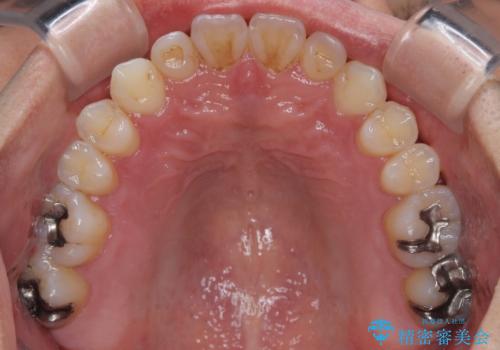

内側に引っ込んだ歯を治したい インビザラインの矯正治療

- 前歯のデコボコとクロスバイトを治したいとのことで来院された患者様です。

上下顎ともに歯列全体の側方拡大とIPR(歯と歯の間を削る)によってデコボコとクロスバイトが解消するように設計し、インビザラインにより治療を行うこととしました。